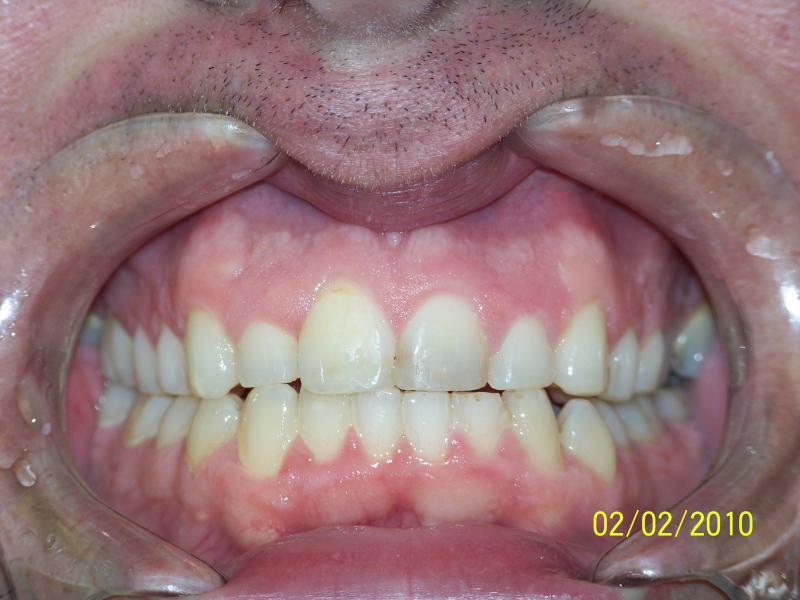

INVISALIGN, 16 months, 2 series of aligner to correct the anterior cross bite, to intrude the over erupted and extremely crowded lower incisors. COSMETIC DENTISTRY, leveling of incisal edges, gingival tissue contouring, and cosmetic bonding.

Cosmetic Dentistry, Mid-line Asymetry, Severe Crowding